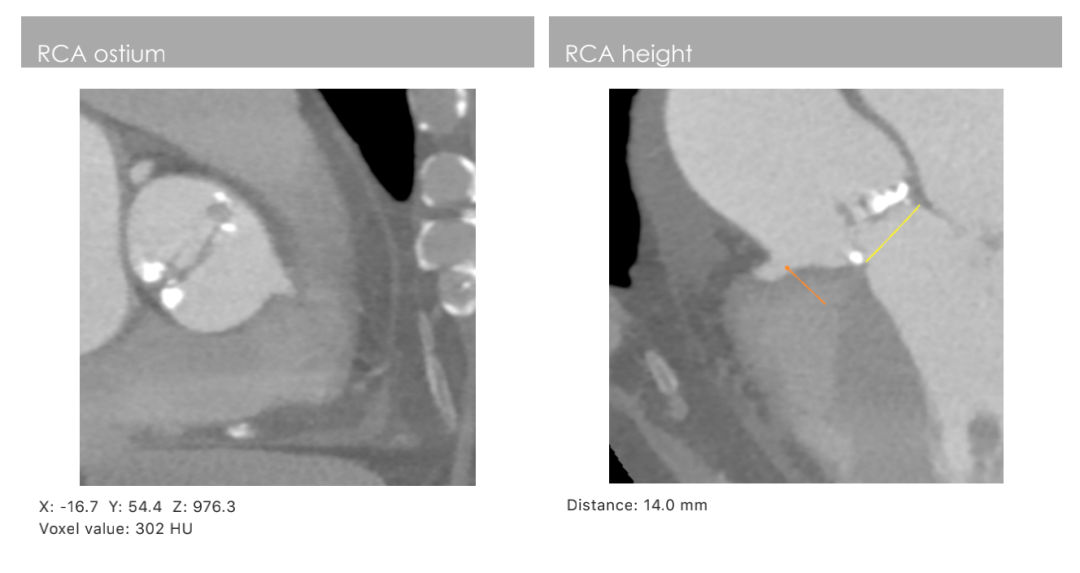

主动脉CT

主动脉瓣环周长79.6mm(平均直径25.4mm),流出道周长87mm(平均直径27.7mm),左冠高度:15.2mm,右冠高度:14mm,主动脉窦宽26.7mm/40.1mm、STJ周长:133.8mm(平均直径42.6mm)高度24.1mm,升主动脉周长:165.5mm(平均直径53mm)。